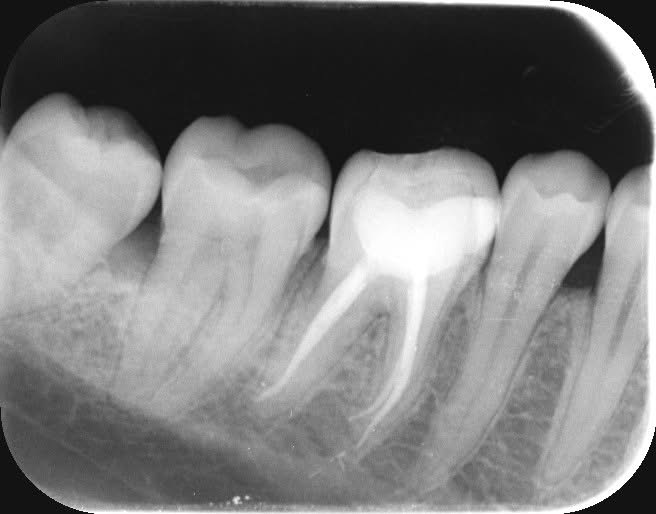

根尖までファイルが到達した事を確認するためにレントゲンを撮り、根尖孔の太さや根管の長さを確認しました。

根管形成後、十分に根管洗浄を行いバイオセラミックにて根管充填をしました。

根尖まできちんと根管充填材であるバイオセラミックが入っている事が確認できます。(根管充填後のレントゲン写真)